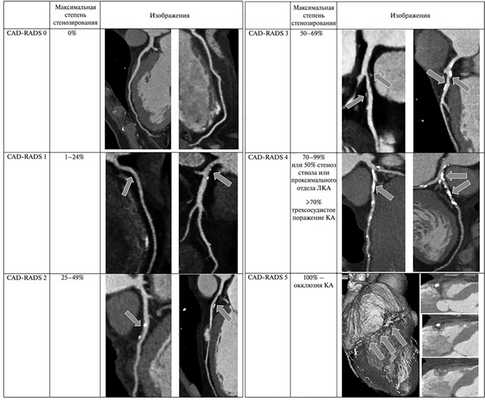

Еще одним фактором, «тормозящим» активное клиническое применение КТ-КА, является отсутствие широкого использования всех диагностических возможностей метода в рутинном протоколировании результатов исследования. Классической радиологической классификацией атеросклеротических поражений коронарных артерий является система CAD-RADS (Coronary Artery Disease — Reporting and Data system), однако в реальной клинической практике эта система используется не всегда. CAD-RADS — система описания, обработки и стандартизации данных КТ-коронарографии с целью обеспечения оптимальной тактики ведения пациента при патологии коронарного русла. Градация CAD-RADS варьирует от 0 до 5 (см. рисунок, таблицу).

Тяжесть атеросклеротического поражения коронарных артерий по системе CAD-RADS.

CAD-RADS — Coronary Artery Disease — Reporting and Data system; КА — коронарные артерии; ЛКА — левая коронарная артерия.

Тактика ведения пациента в зависимости от тяжести атеросклеротического поражения коронарных артерий по системе CAD-RADS